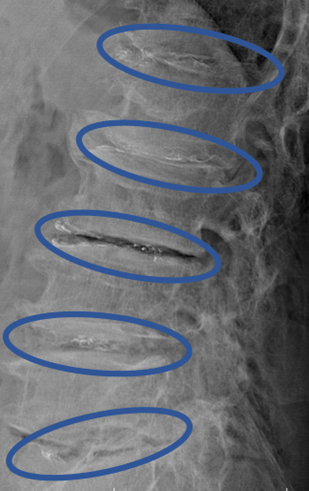

DiscoGelを入れた後の画像になります。

治療は 50分程度で終了

回復室で休憩後、歩いて帰院されました。